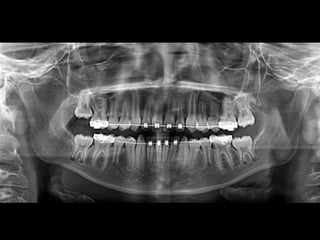

RADIOGRAFÍAS PANORÁMICAS